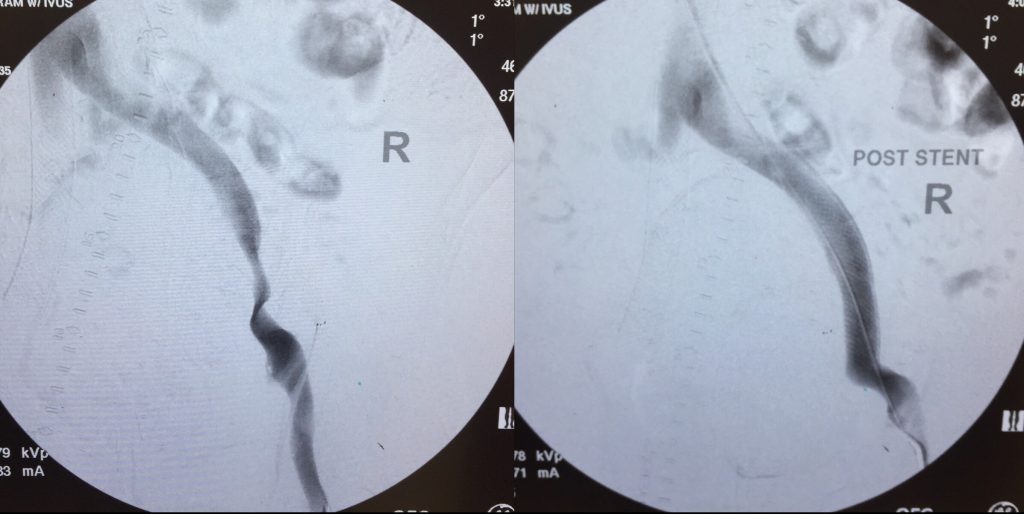

59 year old dialysis patient with right lower extremity pain at rest. Patient presented with multifocal high grade stenoses and long segment chronic total occlusion in the right thigh artery. This was successfully repaired by Dr. Shirey at his state of the art outpatient facility and the patient’s leg pain has resolved.